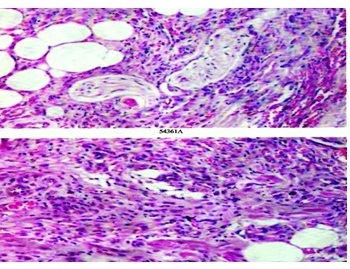

- Figure 5 Micro-section from plaque shows dilated, irregular new vessels and pre-existing vessels in the dermis. Also seen are few scattered spindle cells (H & E× 400).

- Figure 6 Micro-section from nodule shows fascicles of spindle cells in the dermis and superficial subcutis.